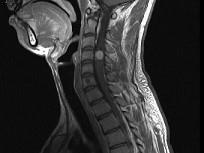

问题 男,24岁,颈部疼痛,并右上肢麻木,以手部明显,请根据所提供图像,选择最可能的诊断()

选项 A.(颈4~5)神经鞘瘤 B.(颈4~5)脊膜瘤 C.(颈4~5)海绵状血管瘤 D.(颈4~5)血管母细胞瘤 E.(颈4~5)胶质瘤

答案 A